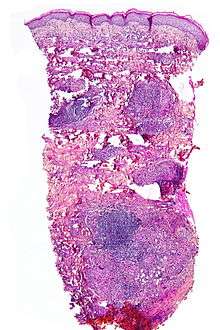

Although the exact cause of this condition is not known, it is an inflammatory disorder characterised by collagen degeneration, combined with a granulomatous response. It always involves the dermis diffusely, and sometimes also involves the deeper fat layer. Commonly, dermal blood vessels are thickened (microangiopathy).[3]

NL is diagnosed by a skin biopsy, demonstrating superficial and deep perivascular and interstitial mixed inflammatory cell infiltrate (including lymphocytes, plasma cells, mononucleated and multinucleated histiocytes, and eosinophils) in the dermis and subcutis, as well as necrotising vasculitis with adjacent necrobiosis and necrosis of adnexal structures. Areas of necrobiosis are often more extensive and less well defined than in granuloma annulare. Presence of lipid in necrobiotic areas may be demonstrated by Sudan stains. Cholesterol clefts, fibrin, and mucin may also be present in areas of necrobiosis. Depending on the severity of the necrobiosis, certain cell types may be more predominant. When a lesion is in its early stages, neutrophils may be present, whereas in later stages of development lymphocytes and histiocytes may be more predominant.